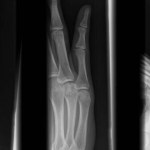

Volar Plate Fracture

The volar plate is a fibrocartilaginous band that strengthens the volar aspect of the joint capsule of...